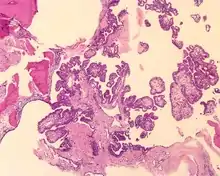

Pathology findings

Tumors range from several millimeters up to 10 cm, with larger tumors more frequently seen in older patients. If the tumor is bilateral, it is almost always seen in a VHL patient. The tumor destroys the mastoid air spaces and extends into the middle ear and/or posterior cranial fossa.[1][3]

The microscopic appearance shows an unencapsulated, destructive growth, remodeling and invading bone. The tumor is arranged as simple, broad, non-complex papillary projections without large cystic spaces. The spaces are often fluid filled, have extravasated erythrocytes and/or inspissated material. The cells are cuboidal, usually single layered along the papillary structures, showing indistinct cell borders. The nuclei are round and hyperchromatic.[1][3][10][11]